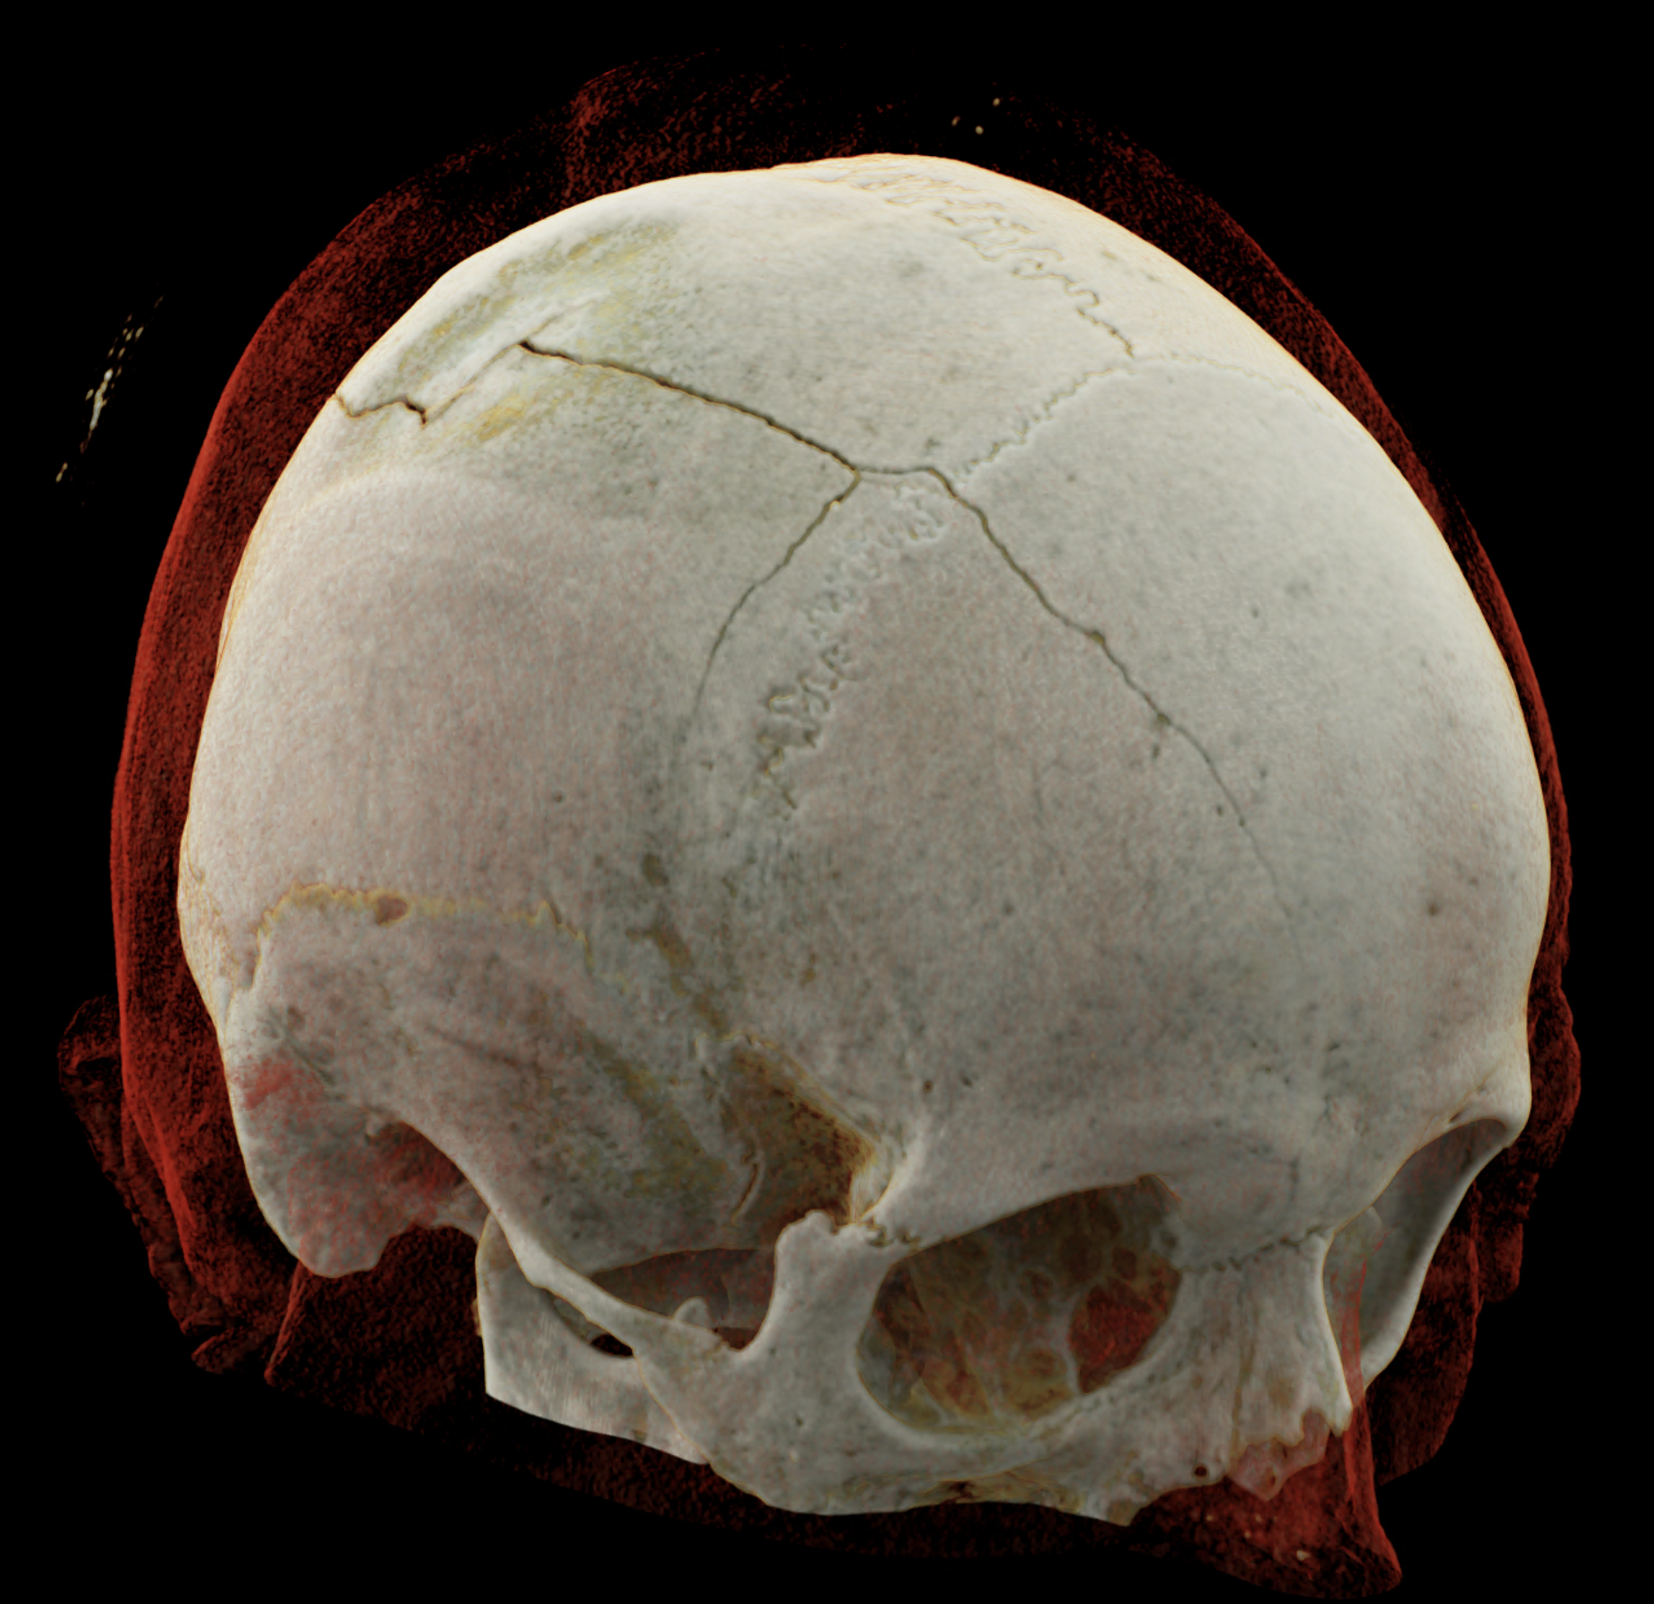

Three-dimensional reconstructions also show a complex skull fissure that extends from the frontal bone to the parietal and temporal bones.

volume rendered technique – display of the fissure course